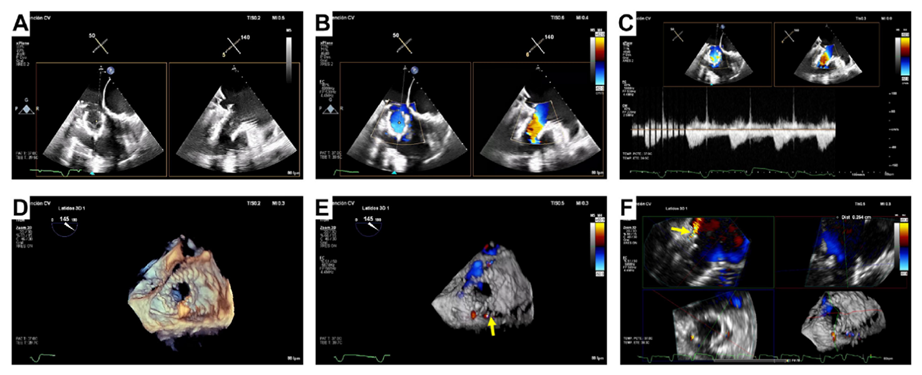

基線經胸和經食道超聲